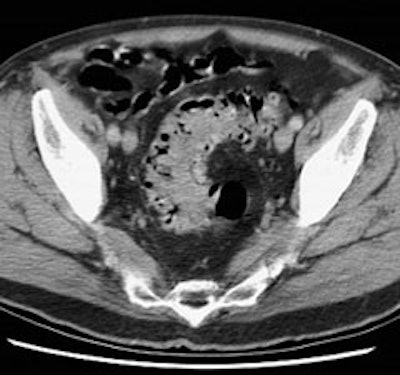

3- Renal/Urinary bladder- Unlike glucose, FDG is filtered by the glomerulus and not resorbed [54]. Hydration and frequent voiding promote diuresis and help to decrease the radiation dose to the genitourinary tract [4]. The use of IV hydration and IV lasix (0.5 mg/kg up to 40 mg with 3 successive urinary bladder voidings) can help to decrease/clear ureteral and urinary bladder activity in cases in where there are equivocal pelvic findings [153].

|